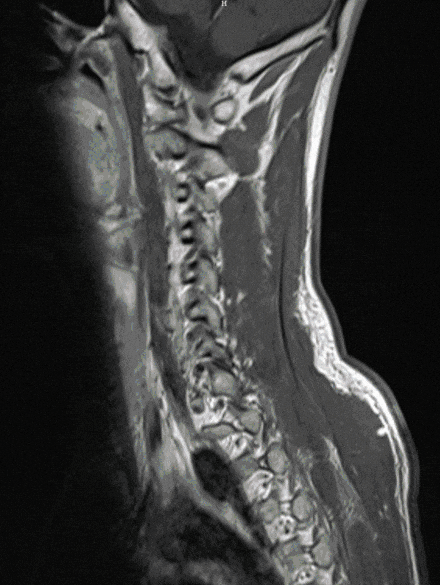

Neurinomas and neurofibromas are relatively common tumors that can lead to massive compression of the spinal cord from the outside. Not infrequently, these tumors occur in the context of hereditary diseases (neurofibromatosis). They threaten the function of the spinal cord and lead to the occurrence of pain or neurological deficits.

The therapy of choice is usually surgical removal. We will be happy to advise you about this disease and the treatment modalities.